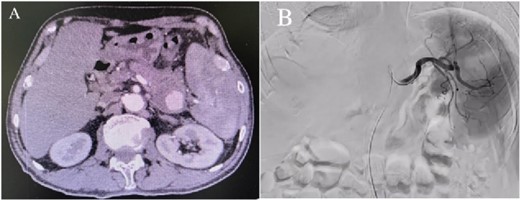

Enhanced CT showed regional portal hypertension and CP invading the splenic artery and forming a pseudoaneurysm of the splenic artery, partially invading the jejunum (Fig. 1A). Subsequent celiac angiography confirmed a pseudoaneurysm originating from the splenic artery (Fig. 1B). Combined with the characteristics of the patient’s history and the results of angiography, the patient was diagnosed with gastrointestinal bleeding: pseudoaneurysm of the splenic artery and CP. After excluding relevant contraindications, abdominal arteriography and embolization were performed simultaneously. So further intubation until confirmation of splenic artery angiography, we used a coil to embolize the pseudoaneurysm. At that time, repeat angiography showed that the main splenic artery and the pseudoaneurysm showed no further enhancement (Fig. 2B). Subsequent CT scan 6 days after the embolization showed no filling of the pseudoaneurysm (Fig. 2A), and he was discharged 2 days later. After 6 months of follow-up, the patient recovered well and returned to normal work and life.

(A) Abdominal CT scan showed the presence of a SAP. (B) Celiac angiography confirmed that the main trunk of the splenic artery showed contrast agent overflow and the formation of a pseudoaneurysm of the splenic artery.